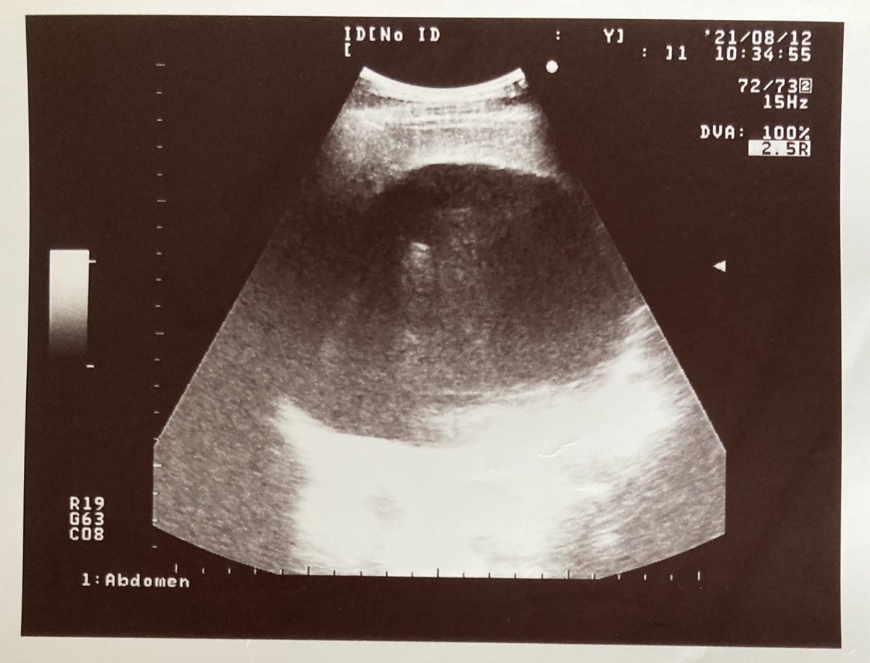

苦苓給母親看自己肝臟腫瘤的超音波照片,「結果我媽一開始竟然以為是我老婆懷孕,高興得不得了。後來弄清楚是腫瘤後,她也只說了句:反正你不准比我先死!」讓他又是好笑,又是五味雜陳。

苦苓的肝臟超音波照片,腫瘤卻一度被媽媽誤認為是老婆懷孕。